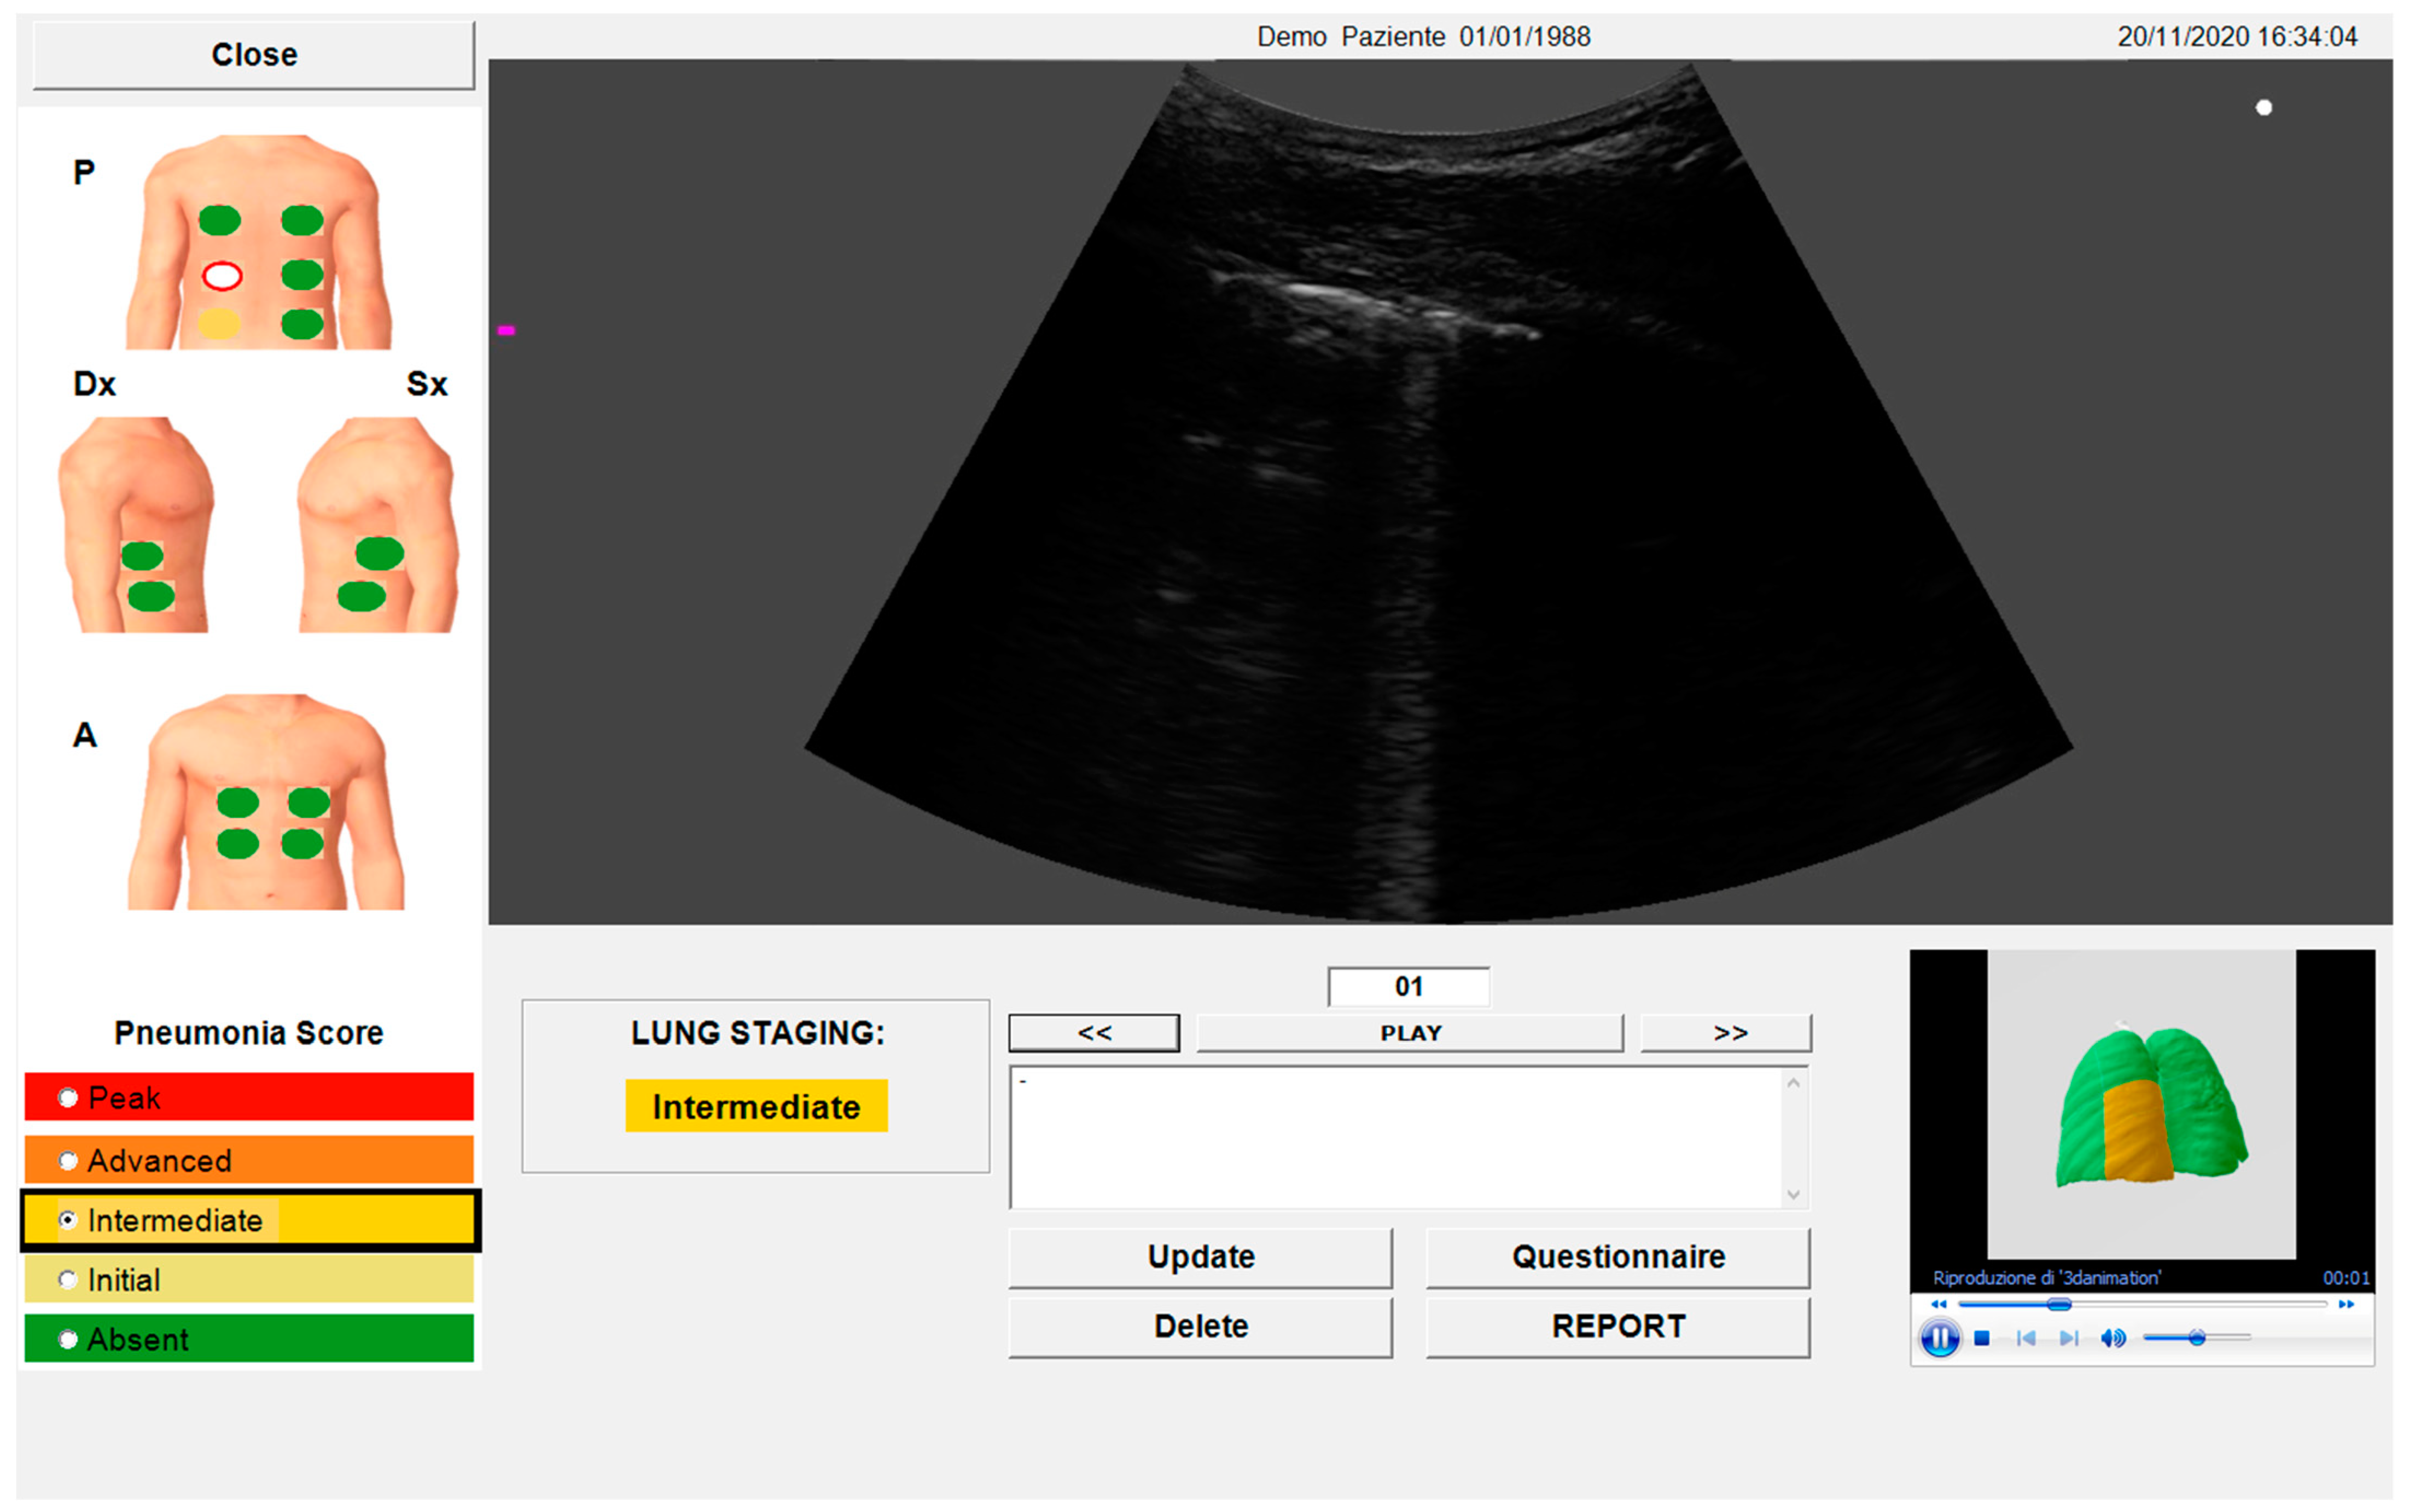

2.4. Automated Algorithm

- Lombardi, F.A.; Franchini, R.; Morello, R.; Casciaro, E.; Ianniello, S.; Serra, M.; Satriano, F.; Mojoli, F.; Mongodi, S.; Pignatelli, D.; et al. A New Standard Scoring for Interstitial Pneumonia Based on Quantitative Analysis of Ultrasonographic Data: A Study on COVID-19 Patients. Respir. Med. 2021, 189, 106644. [Google Scholar] [CrossRef]